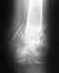

Перелом с двумя осколками, фиксация по Веберу,средний осколок через месяц имеет смещение наружу, крайний отросток - вверх по локтю и немного внутрь. Предлагают фиксацию пластиной.

Сейчас (5 недель) на снимках такая картинаhttp://tinyurl.com/c26vlkrна снимках сбоку и в сечении видна заметная репозиция осколков (снимки 6-8).Особенно непосредственно около сустава, внешняя поверхность под петлёй вроде совмещена, а изнутри - ступенька в несколько миллиметров.Ходил в местную клинику, врач говорит, что осколка два и средний осколок неправильно центрировался петлёй, что рабочая поверхность сустава сейчас неровная, высокая вероятность развития артрита.Предлагают, пока перелом свежий (5 недель), поправить и зафиксировать осколки блокирующей пластиной.Операция для меня будет бесплатной.Я понимаю так, что необходимости в операции нет, но будет ли от дополнительной фиксации толк и не будет ли хуже?

• Кликните для загрузки файла 6.jpg

110KB (113652 bytes)